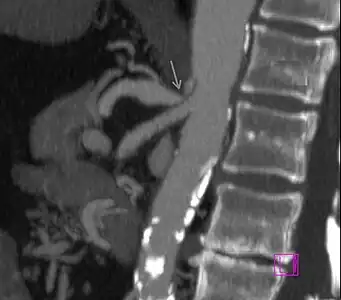

Further evaluation and confirmation can be obtained via angiography to investigate the anatomy of the celiac artery.[5] Historically, conventional angiography was used, although this has been largely replaced by less invasive techniques such as computed tomography (CT) and magnetic resonance (MR) angiography.[2][5] Because it provides better visualization of intra-abdominal structures, CT angiography is preferred to MR angiography in this setting.[5] The findings of focal narrowing of the proximal celiac artery with poststenotic dilatation, indentation on the superior aspect of the celiac artery, and a hook-shaped contour of the celiac artery support a diagnosis of MALS.[2] These imaging features are exaggerated on expiration, even in normal asymptomatic individuals without the syndrome.[2]

Proximal celiac artery stenosis with poststenotic dilatation can be seen in other conditions affecting the celiac artery.[2] The hook-shaped contour of the celiac artery is characteristic of the anatomy in MALS and helps distinguish it from other causes of celiac artery stenosis such as atherosclerosis.[2] This hooked contour is not entirely specific for MALS however, given that 10–24% of normal asymptomatic individuals have this anatomy.[2]

Median arcuate ligament syndrome-a)Stenosis and aneurysm of celiac artery because of compression arrows b)severe stenosis and poststenotic dilatation white arrow c) median arcuate ligaments arrows and gastric mucasal thickening -

Coeliacus compression